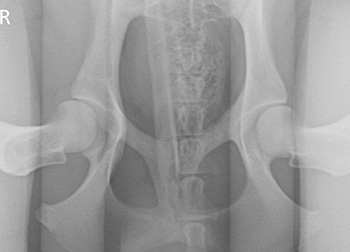

PennHIP 검사는 강아지 고관절 이형성(Canine hip dysplasia, CHD)을 조기에 진단할 수 있는 진단 방법입니다. 강아지 고관절 이형성은 주로 대형견의 고관절에서 나타나는 유전적 질환으로 선천적인 고관절의 불안정성으로 인해 추후에 관절염으로 진행되어 통증, 파행 등 다양한 임상증상이 유발할 수 있습니다. PennHIP 검사는 강아지 고관절 이형성을 가진 환자가 관절염으로 진행되지 않았을 확률이 높은 생후 16주령부터 조기에 검진이 가능하고, 따라서 초기에 질환의 관리를 가능하게 합니다. PennHIP은 스포츠, 훈련 등을 필요로 하는 경우, 교배 목적이 있는 경우, 건강검진을 목적으로 하는 경우, 마약탐지견, 구조견 등 사역견의 목적이 있는 경우 등에서 진행될 수 있습니다.